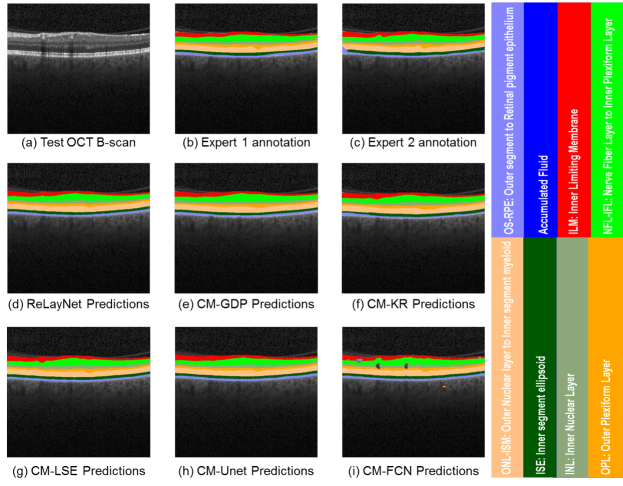

Fig. 7: Layer predictions of Test OCT B-scan with no fluid mass, shown in (a) with the expert 1 annotations in (b), expert 2 annotations in (c), ReLayNet predictions in (d) and predictions of the defined 5 comparative methods in (e-i).

We present a qualitative comparison of ReLayNet in contrast with the comparative methods for two cases: an pathological OCT B-scan with DME (as shown in Figure 6) and for an OCT B-Scan sans fluid accumulation distal from the fovea (as shown in Figure 7).

OCT B-scan without fluid accumulation: The frame presented in Figure 7(a) is representative of a fluid-free OCT scan acquired distal from the fovea. We can consistent performance across the comparative methods. This observation also indicates that the comparative methods have been trained fairly and the major distinction arises in the presence of pathology where such a objective segmentation tool is often needed.